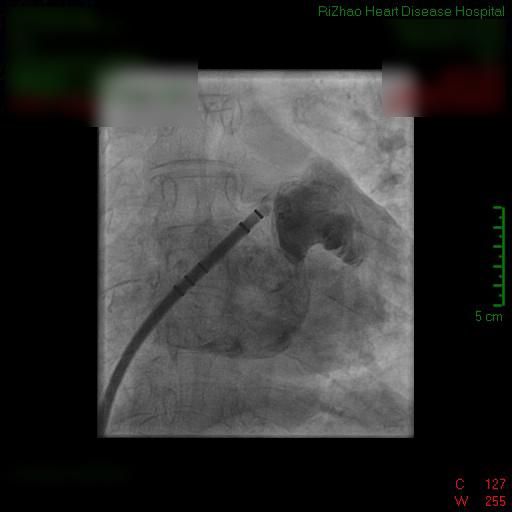

近期,日照心脏病医院/青岛大学日照医院由葛均波院士领衔的博士团队,为一名高龄患者成功实施左心耳封堵术,这是日照地区首次完成左心耳封堵术,标志着医院心内科治疗水平的新进步,可望为更多房颤患者提供更高质量的医疗服务。

经皮左心耳封堵术是近年来发展起来的一种微创、低风险、高即时成功率的介入手术,术中将一个“塞子”样的封堵器塞到左心耳内,将左心耳腔与心房在空间上隔离,消除“血栓滋生”的场所,从而达到预防卒中,降低房颤患者死亡率和致残率的目的。

手术耗时仅仅50分钟,该例手术的成功,意味着秦奶奶血栓栓塞(尤其是脑卒中)的风险被降至最低。据了解,这是日照首次成功开展该项左心耳封堵术。